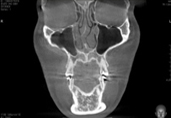

Полная проверка состояния носа благодаря снимкам КТ.

Благодаря 3Д-КТ снимкам возможно рассмотреть в мельчайших подробностях не только состояние костей носа, но и форму, состояние и размеры мягких тканей вокруг него, что позволяет правильно составить безопасный план операции.

В случае наличия врожденной искривленной перегородки или же искривления перегородки из за приобретенной травмы, то исправление асимметрии позволяет не только улучшить эстетический вид но и решить такие функциональные проблемы как плохое дыхание и т.д.